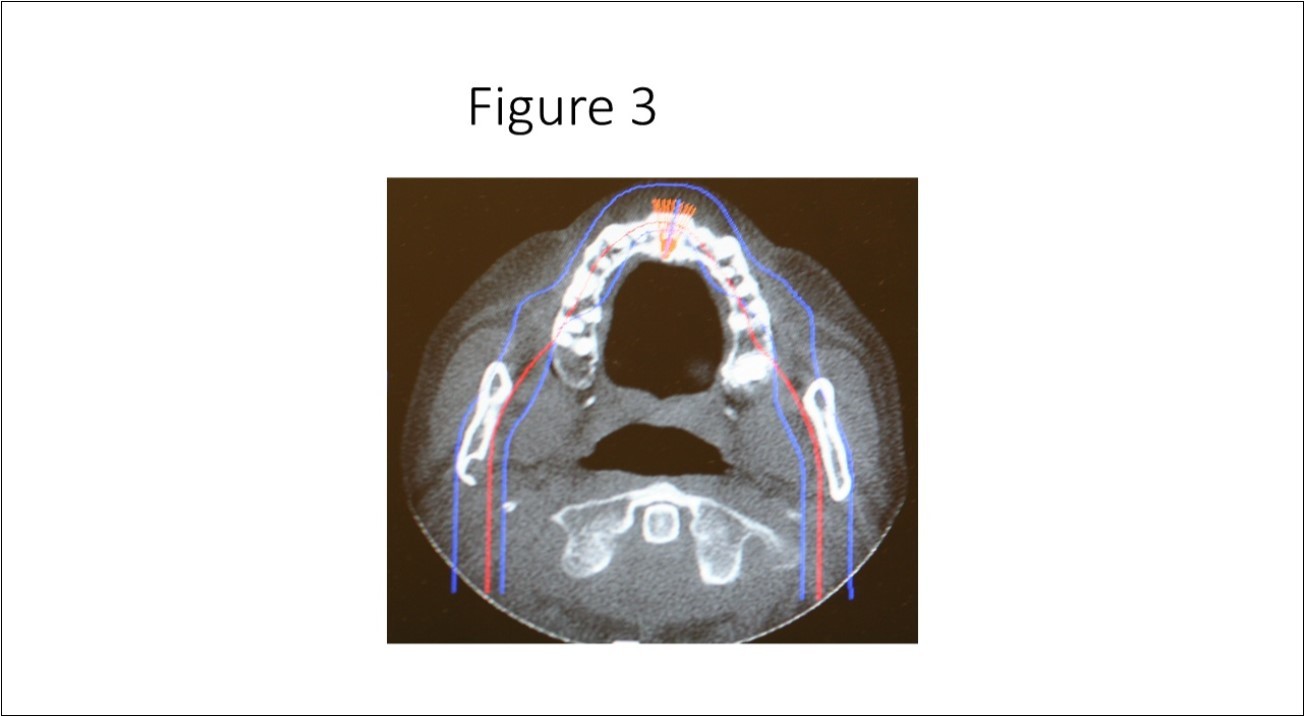

Maxillofacial examination was unremarkable. No facial swelling, masses or asymmetry was observed. The TMJ examination was normal. No pain or tenderness to digital palpation was observed in the right preauricular region. Oral examination of the patient was unremarkable. No trismus was observed as the maximal interincisive opening was greater than 40.0mm. No anterior or posterior open bite was observed. Imagining studies to rule-out intraosseous neoplastic lesions and arrive at a definitive diagnosis consisted of a panoramic radiograph and cone beam CT scan (120 kVp, 5 mA, 7.4 sec). Panoramic radiograph revealed a unilocular, well-circumscribed radiolucency in the right subcondyalar region of the mandible that was close to the posterior border of the condylar neck (Figure 2). Cone beam CT scan (i-CAT FLX, Imaging Sciences, Hatfield, PA) imaging revealed a well-defined unilocular, elliptical shaped radiolucent lesion on the medial surface of the right subcondylar neck of the mandible (Figure 3, Figure 4, Figure 5). The elliptical shaped unilocular lesion involved almost the entire horizontal dimension of the subcondylar neck (Figure 4). Figure 5 shows the three-dimensional CT scan reconstruction (i-CAT FLX, Imaging Sciences, Hatfield, PA) of the medial defect in the subcondylar region of the mandible. Based on knowledge of clinical head and neck anatomy and imaging studies, no treatment was indicated as the diagnosis was consistent with a variant of a Stafne bone cavity of the right subcondylar neck near the parotid gland and not a pathological condition. The patient was informed about the risk of condylar neck fracture due to the critical size of the SBC.

Figure 3.Axial cone beam CT scan showing osseous bone defect with herniation of soft tissue in the medial cortex of the right subcondylar neck of the mandible.

Stafne bone cavity located in the subcondylar region of the mandible is considered a rare variant of the well-described SBC in the mandibular posterior mandible first reported by Stafne in 1942. There is a paucity of published case reports of SBC identified in the subcondylar or ascending ramus of the mandible in the English world medical and dental literature.9,19In a study by Sisman et al 3using computed tomography they concluded that the SBC is due to the presence of aberrant submandibular gland tissue within the osseous defect on the medial surface of the mandible. As it is hypothesized that the submandibular gland tissue is entrapped that leads to an osseous concavity on the medial surface of the mandible, it is also plausible that the parenchymal tissues of the parotid gland can also become entrapped in the developing mandible that leads to a similar osseous concavity (Figure 3) in the subcondylar region of the mandible.20